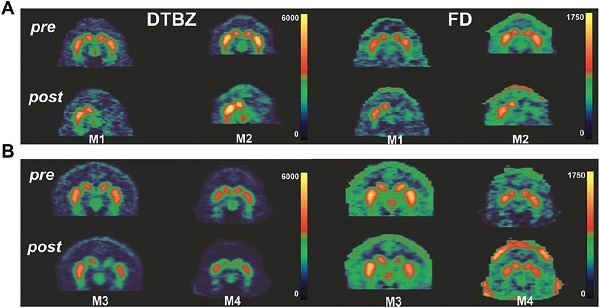

图41.猴子的PET成像图